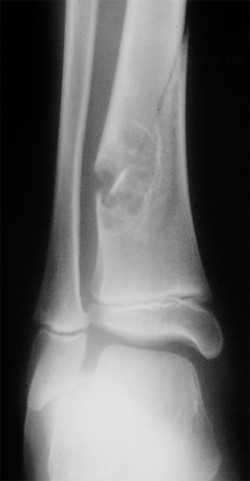

18 yo male patient with R sided leg swelling, bruising and pain

Radiographs were deemed necessary and the patient was sent for x-rays of the lower extremity. Images are provided below.

Questions: What are the significant findings in the radiograph? What is the diagnosis?